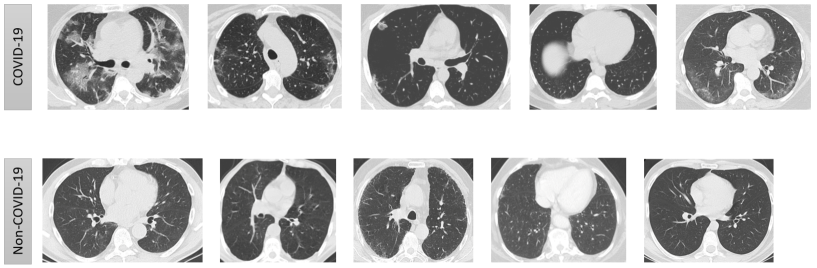

We use a publicly available data set “SARS-CoV-2 CT-scan dataset”, which contains 1252 CT scans that are positive, and 1230 CT scans for patients non-infected for COVID-19 infection. These data is collected from patients in hospitals from Sao Paulo, Brazil and made public in (Angelov & Almeida Soares,, 2020; Soares et al. ,, 2020).

We propose a model based on topological features, these provides a binary classification for COVID and Non-COVID CT-Scans. Our model is an attempt to capture the features as observed by a professional medic. These features are picked up by the topological summaries provided by PDs. Hence making it biologically more interpretable as compared to deep neural networks. Moreover topological techniques do not need plenty of data to train a model. Table 1 compare the average values of the evaluation metrics achieved by different deep networks and our topological model.